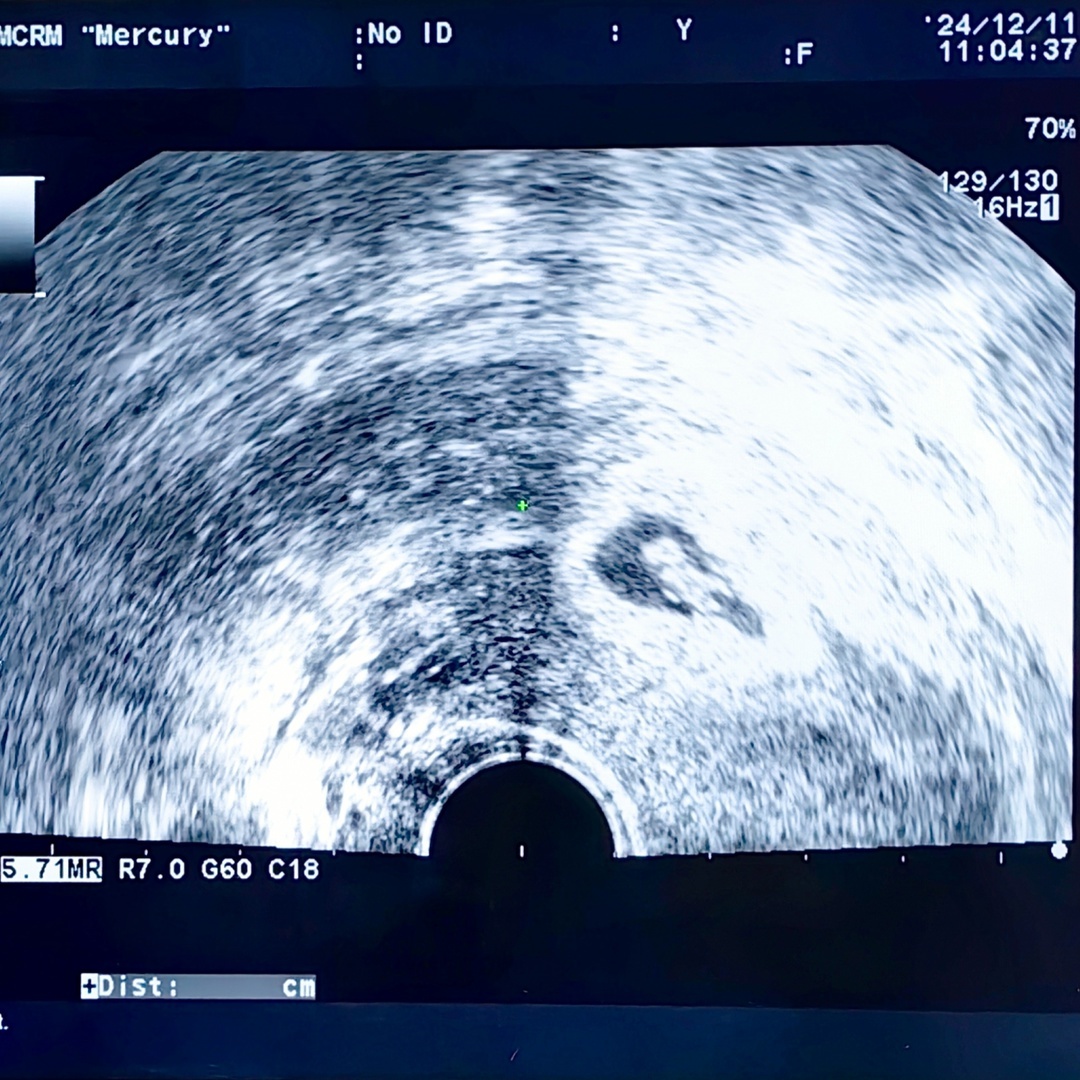

возможность провести две программы ЭКО по ОМС без участия отца. И вот

она радость: на УЗИ увидели, как бьётся сердечко нашего малыша. ⠀